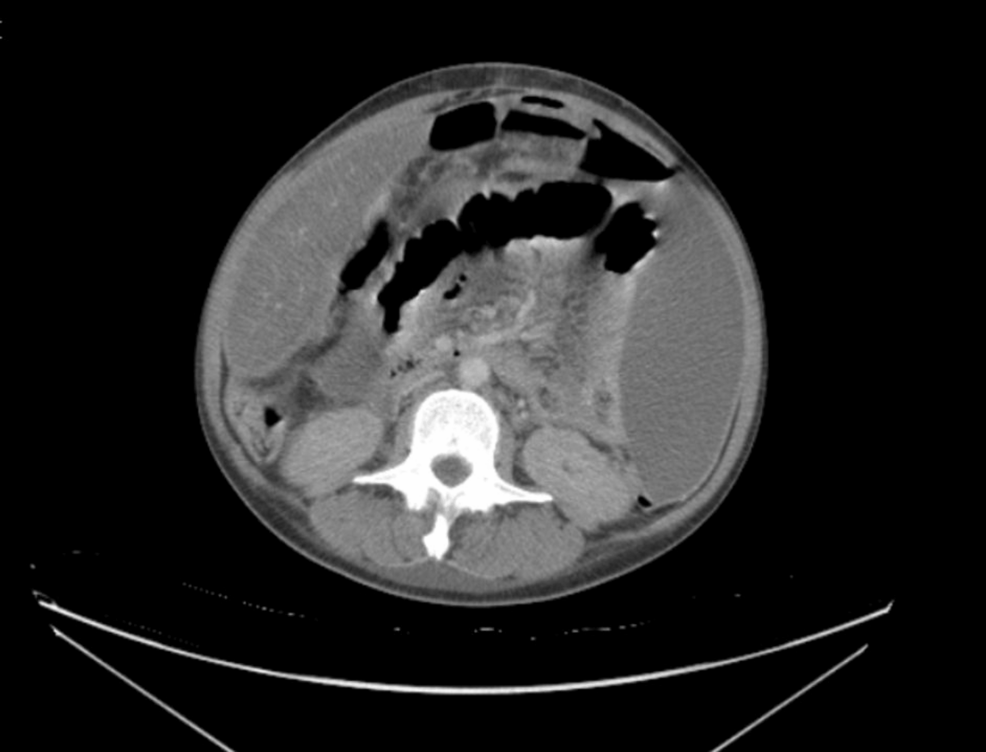

A recent case report published this week in Cureus details a patient with undiagnosed HIV who presented with tuberculosis (TB) peritonitis. This rare extrapulmonary manifestation of TB underscores the critical ... Read More